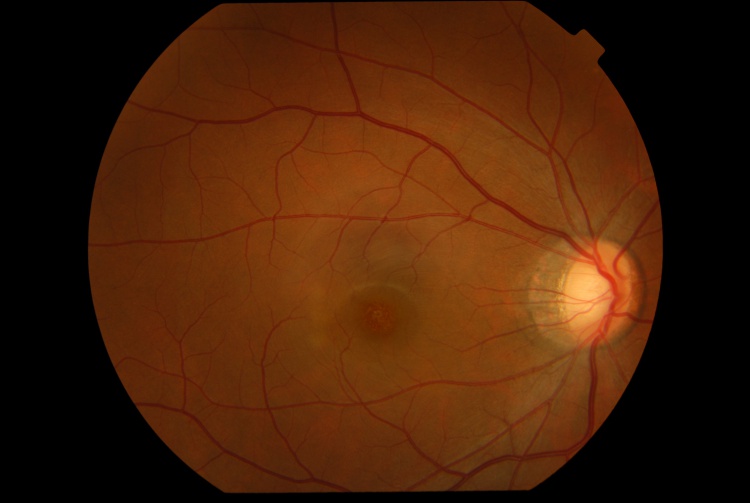

The presenting visual acuity is usually around 20/40 and can range from 20/30 to 20/100.[1] Amsler grid shows a central scotoma.[5] The anterior segment examination is typically unremarkable.[5] Signs of intraocular inflammation are absent.[5] The fundus examination characteristically shows fine pigment stippling in the macula surrounded by a hypopigmented halo (Figures 1 and 2).[4][5][7] A few white dots may also be seen in the macula in the extrafoveal region.[5][8]